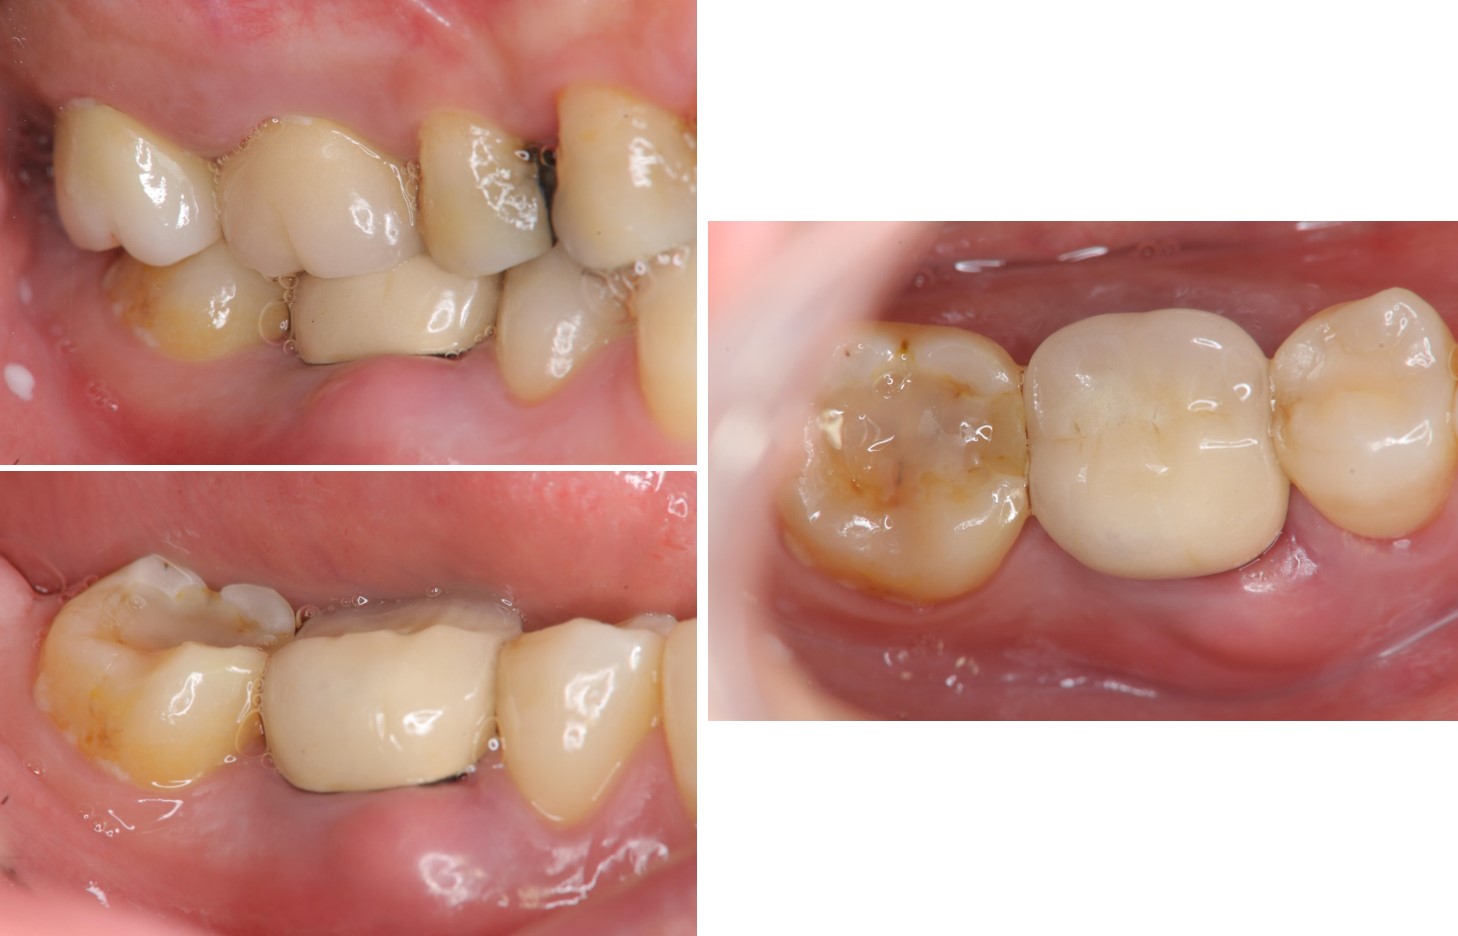

治療後,咬合牙周適應良好

治療後,密合度良好

術前、術後比較

使用單顆植牙,不需修磨正常的牙齒,清潔更方便,且咬合更強。